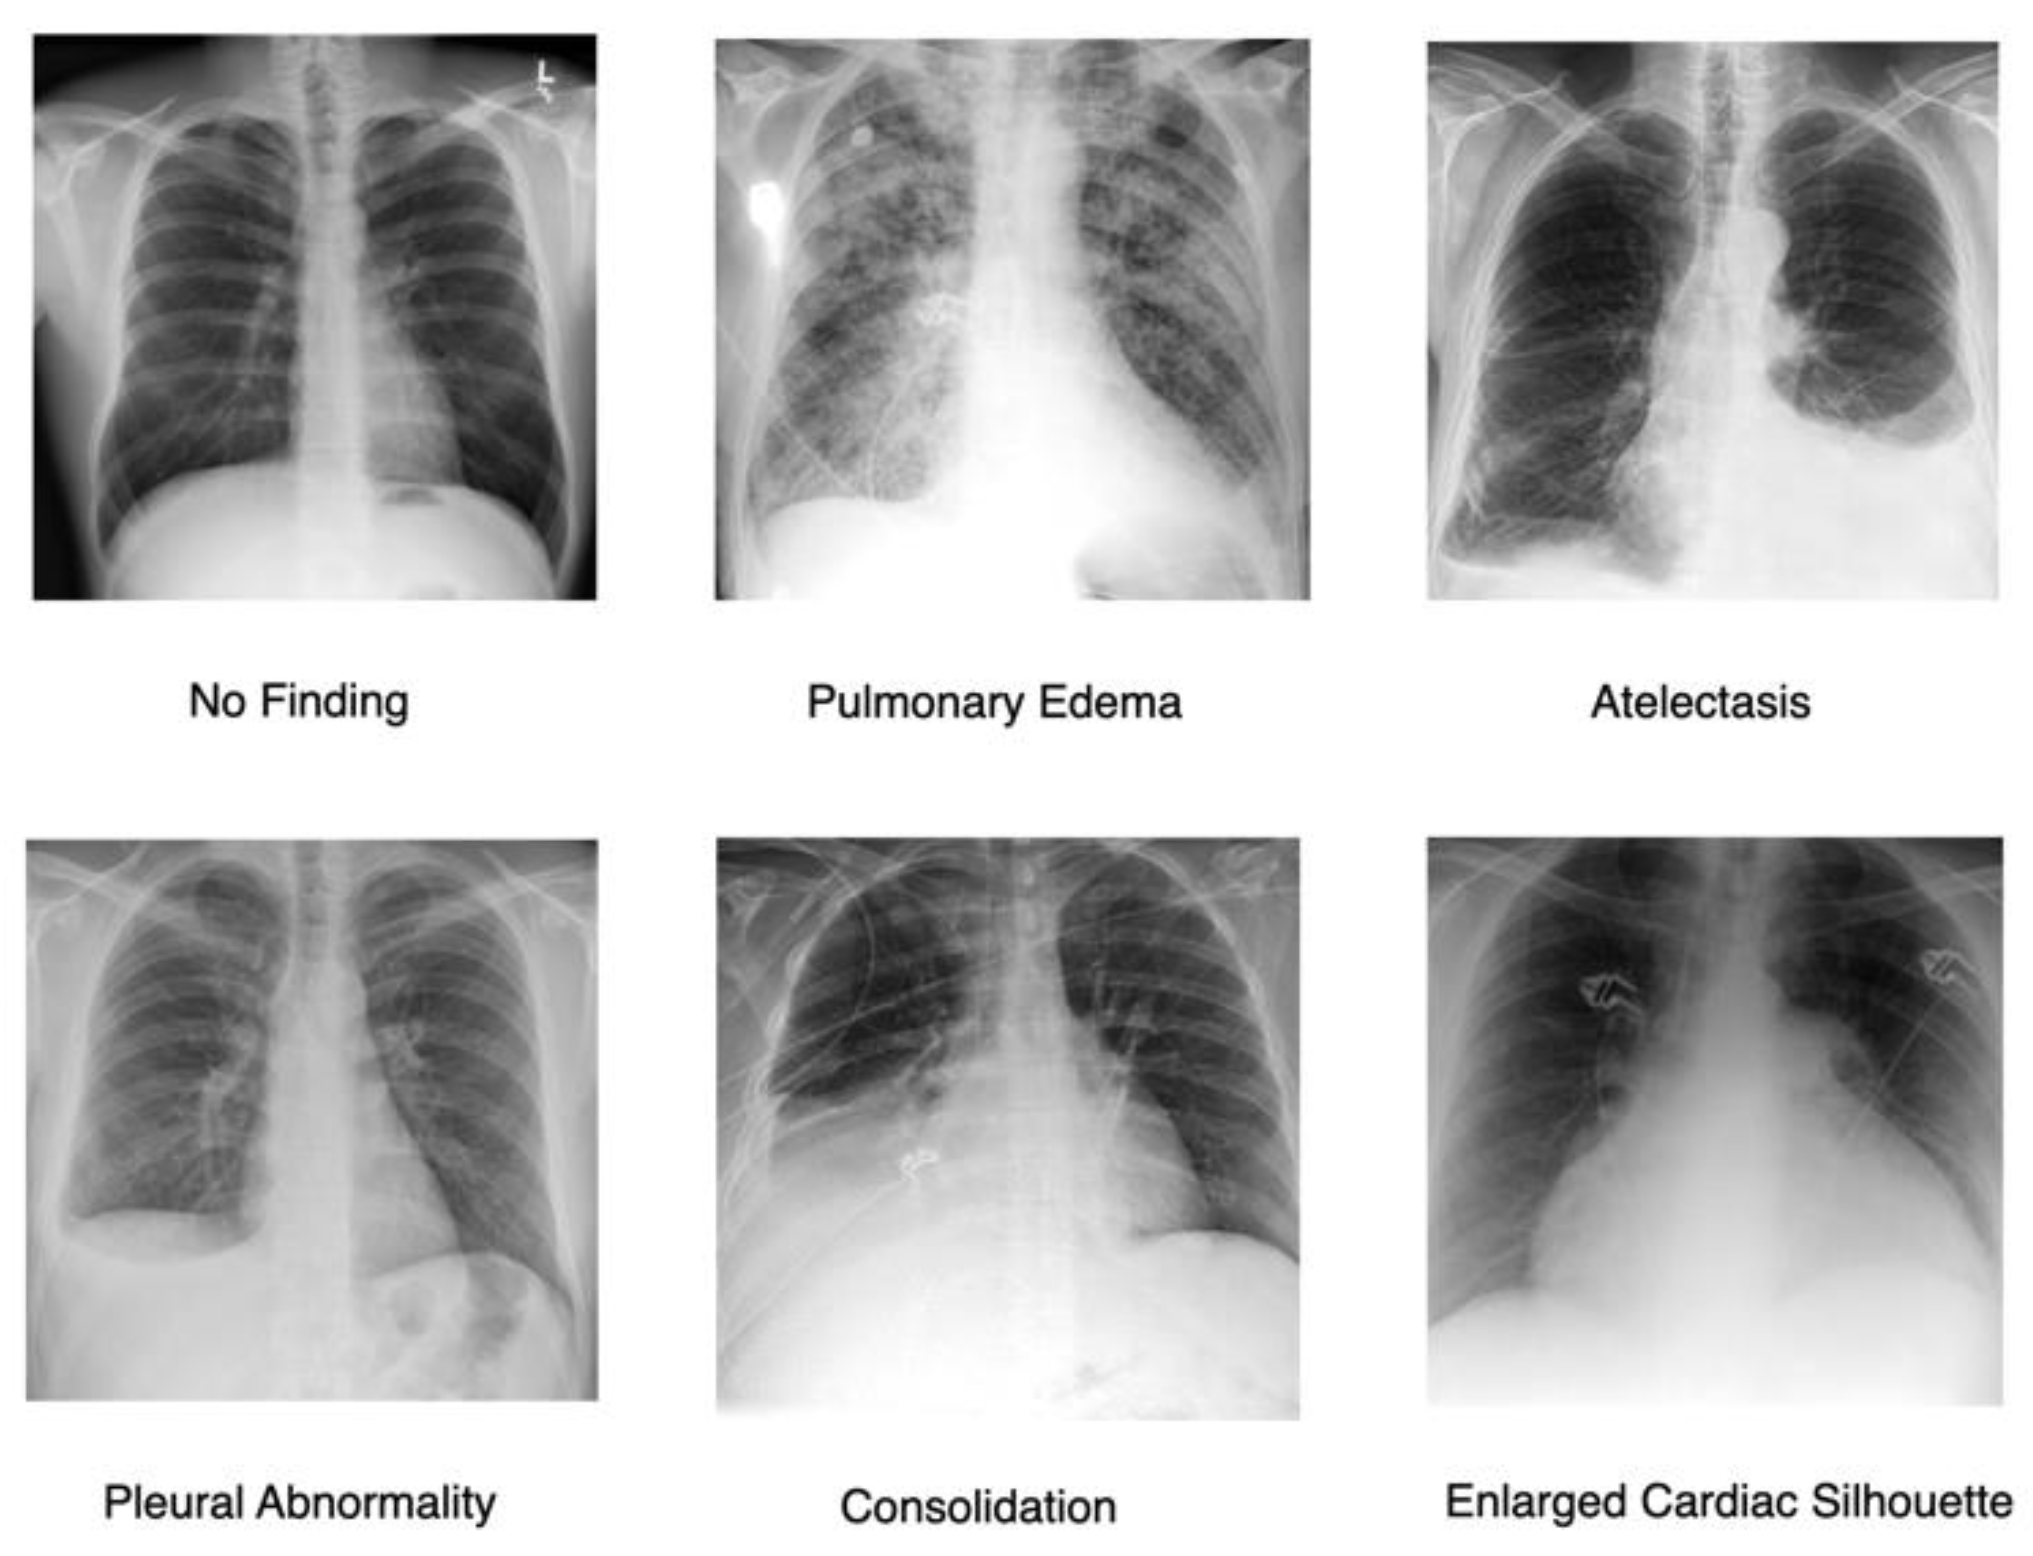

A. Dataset